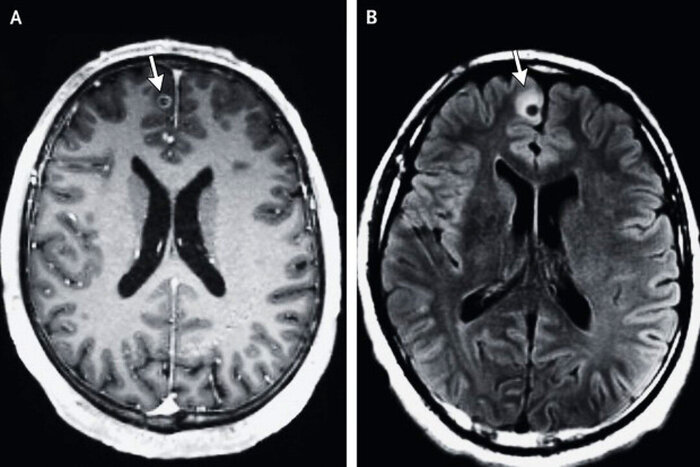

Если же человек заражается яйцами свиного цепня, то он становится для него промежуточным хозяином и тогда внутри человека развиваются финны -- пузыри с зародышами гельминта. Эти пузыри могут оказаться где угодно: от мышечной ткани до головного мозга. Заболевание тогда будет называться цистицеркоз, а если в головном мозге, то нейроцистицеркоз.

Со свиным цепнем дела обстоят хуже, так как его проглоттиды мечут яйца в том числе и в тоном кишечнике хозяина, где личинки преодолевают стенки и также оседают в тканях (где угодно), и в том числе и мозге, что может привести к довольно экзотическому завершению бренного пути хозяина.

Поэтому бычий цепень лечится довольно легко антигельминтовыми препаратами, а вот свиного цепня мало убить, нужно ещё убить и финны в тканях, а в некоторых случая ещё и требуется сложная хирургическая операция, если финны попали в мозг, или жизненно важный орган.